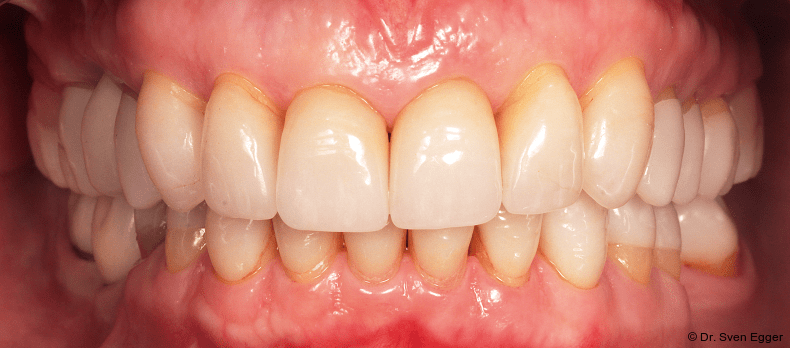

- Zahnlänge: Die Verlängerung der gesamten Oberkieferfront um ca. 1 mm empfindet die Patientin als sehr attraktiv, das entspannte Lächeln zeigt fast die gesamte Frontzahnreihe. Der Schneidekantenverlauf folgt der Konkavität der Unterlippe.

- Zahnform: Die größeren und längeren Schneide- und Eckzähne sowie die kleine Stellungskorrektur der beiden seitlichen Schneidezähne fügen sich harmonisch in das Gesamtbild der Restbezahnung ein und schenken der Patientin ein attraktives Erscheinungsbild (Abb. 15).

- Form und Größe, Charakterisierung durch den ausführenden Zahntechniker (Transparenz, Transluzenz) sowie die Oberflächenstruktur (Textur) der keramischen Veneers zeigen ein ansprechendes Erscheinungsbild. Das Längen-Breiten-Verhältnis beträgt nun circa 80 Prozent (Länge 11 mm, Breite 8 mm).

- Zahnstellung: Die leicht nach distal rotierten seitlichen Schneidezähne konnten durch die Einzelzahnrestaurationen etwas ausgeglichen werden. Durch die „Verlängerung“ der Eckzähne konnte gezielt eine gute Front-Eckzahn-Führung in die Veneerrestaurationen eingearbeitet werden.

- Zahnfarbe: Die Zahnfarbe entpricht ganz den Vorstellungen der Patientin (A2, VITA).

Zusammenfassung der ästhetischen Problematik: Es zeigt sich nun hinsichtlich der Länge (Lächeln), Form, Farbe, Stellung der Zähne sowie der rosa Ästhetik ein ansprechendes dentogingivales Erscheinungsbild. Die unteren Frontzähne haben leichten Kontakt auf den Palatinalflächen der oberen Eck- und Schneidezähne. Der Overbite beträgt 4 mm. Der Overjet 2 mm (Abb. 16+17).